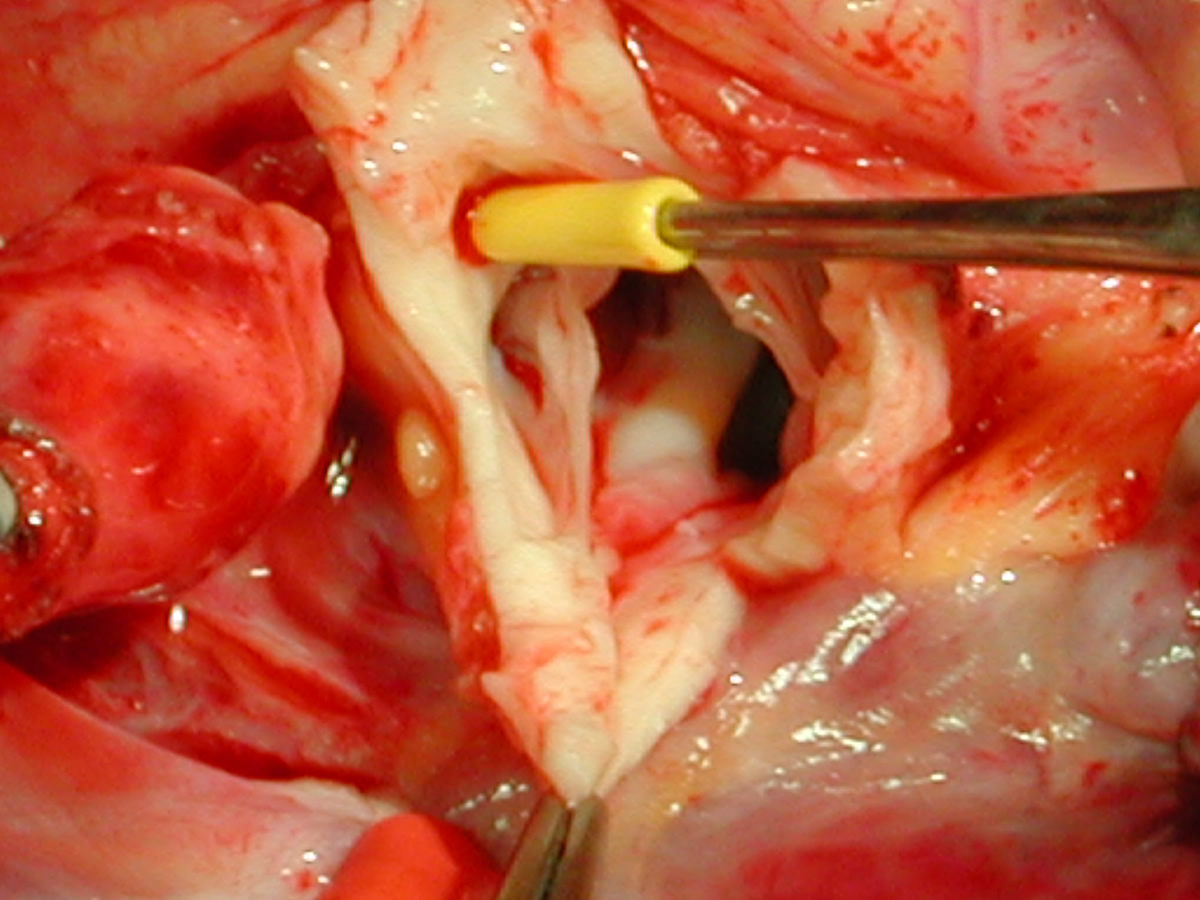

Figures 20 & 21: Third incision has been made to the right of the left coronary orifice. They yellow plastic suture boot on the pickup is pointing out the left coronary orifice. Figures 22 & 23: Proximal ascending aorta now opens widely, revealing the right and left coronary orifices and the normal trileaflet aortic valve below.